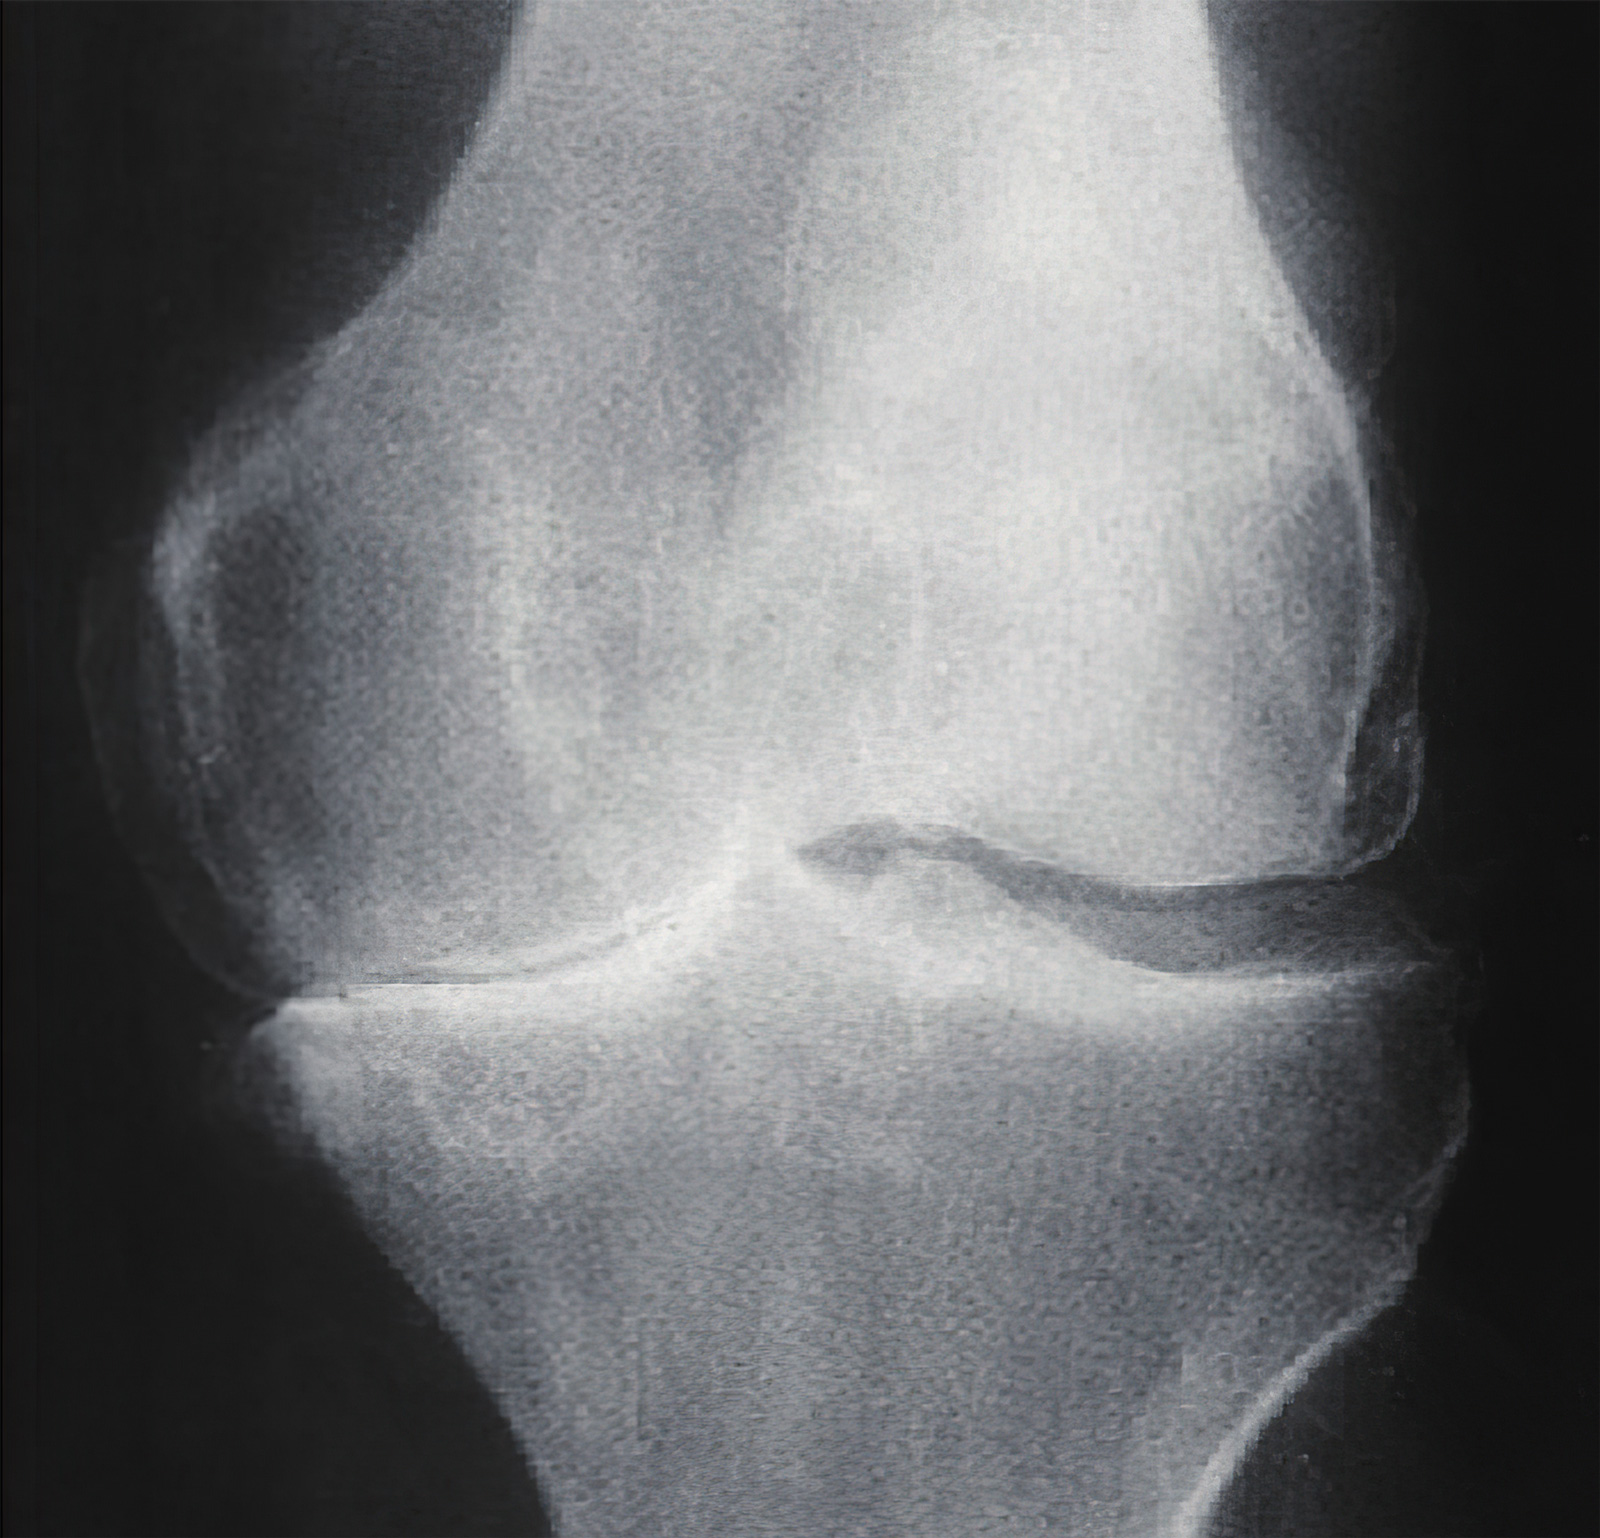

- 患者关节间隙严重狭窄,甚至以及骨性强直,镜下操作困难不宜手术;

关节间隙狭窄者不宜关节镜手术